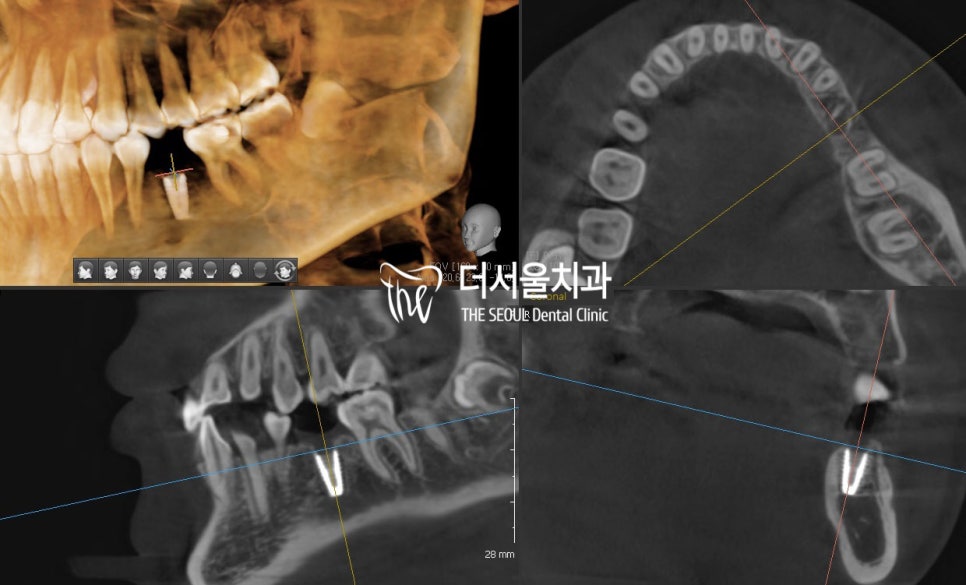

픽스처 식립 후에는 3차원 CT를 이용하여

올바른 위치에 곧게 식립되었는지 확인합니다.

건강한 치조골 사이에

단단하게 심어진 게 보이시나요?